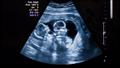

هل تريدين إنجاب توأم؟ إليك بعض النصائح

التوائم الأخوية غير المتماثلة هي النوع الأكثر شيوعًا للتوائم، حيث تمثل حوالي 80٪ من جميع حالات الحمل بتوأم، وتحدث التوائم الأخوية عندما تُطْلَق بويضتان من المبيض في الوقت ذاته، ويتم تخصيب كل منهما بحيوان منوي مختلف، ونتيجة لذلك، يكون التوأمان غير متشابهين في المظهر أو الجنس.

أما النوع الثاني فهو عندما تنقسم البويضة المخصبة إلى قسمين، لتشكل جنينين في الرحم، ويُعرف بالتوائم المتماثلة.